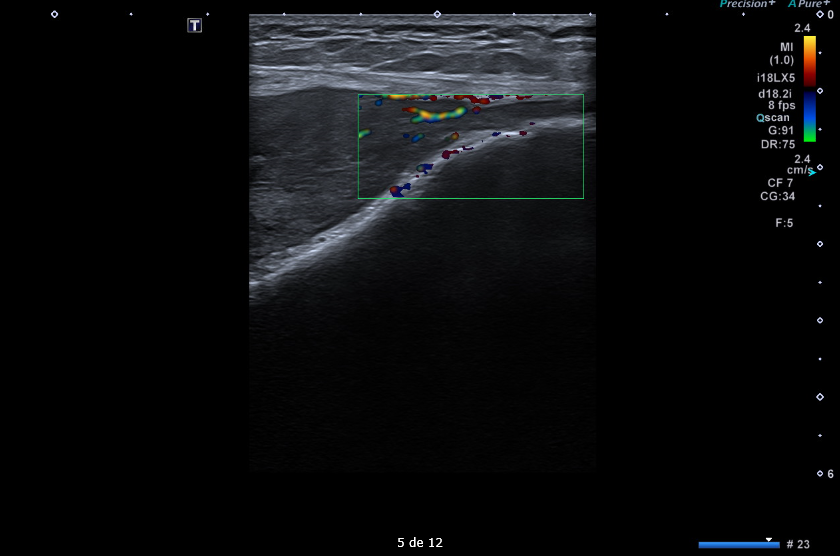

Masa sólida de partes blandas de 5 x 9 x 14 cm en compartimento femoral anterior, en profundidad al recto femoral y vastos medial y lateral. Engloba desde el tercio medio de la diáfisis hasta la rótula. Presenta polos sólidos vascularizados y zonas quísticas/necróticas.